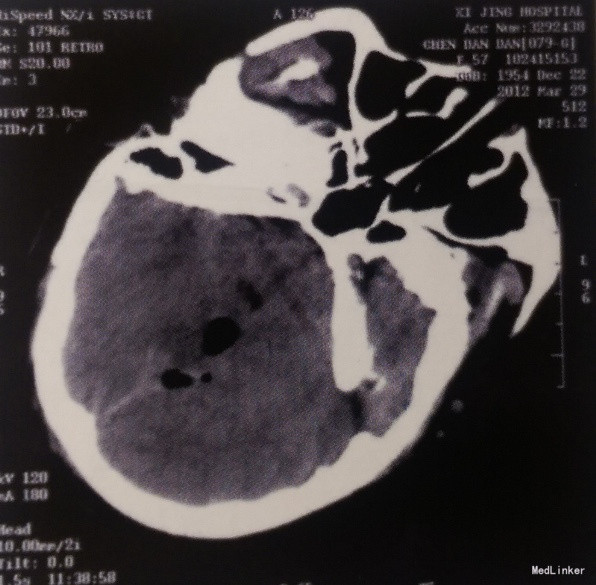

1.本例肿瘤位于小脑幕下,累及双侧小脑半球,主体位于左侧,部分位于右侧。体积巨大,基底广泛,血供丰富。毗邻双侧横窦、窦汇和直窦,压迫双侧小脑半球,第四脑室受压继发轻度梗阻性脑积水。手术风险大。 2.本例采用枕下正中入路,骨窗范围充分,剪开硬脑膜即可见肿瘤及受压的双侧小脑半球。在显微镜下仔细分离肿瘤与周围小脑及静脉窦边界,一面充分电凝止血,一面分块切除肿瘤,并彻底烧灼肿瘤基底小脑幕。最终完全切除肿瘤,术中出血少,未输血。患者术后恢复顺利,伤口如期拆线,无并发症及附加神经功能障碍发生。术后头痛症状消失,术后复查CT和增强MRI提示肿瘤完全切除,无复发,手术效果良好。